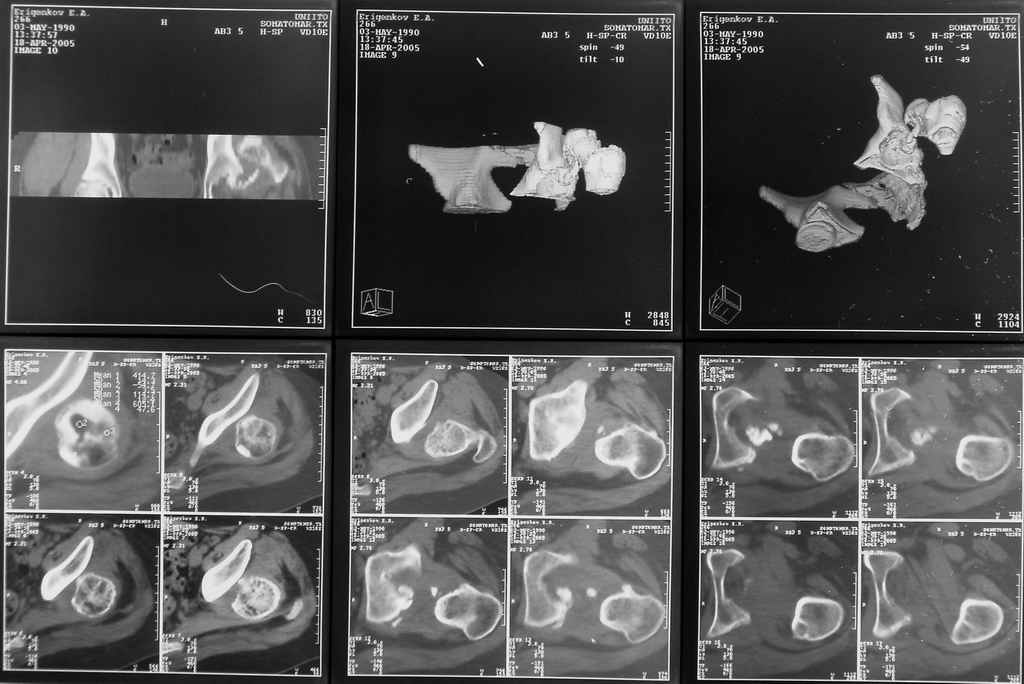

Бедро было синтезировано пластиной и успешно срослось. Как поступить сейчас с вывихом? По КТ видны интерпонированные отломки, впечатление что это фрагменты головки бедра. Поделитесь, пожалуста, опытом. Спасибо.

По-моему варианты с вправлением вывиха бесперспективны, вследствие явных признаков (КТ) асептического некроза головки. Все равно повторной операции - эндопротезирования - не избежать. А оперировать по старым рубцам потом будет сложнее. Поэтому, целесообразным представляется все-таки первичное тотальное эндопротезирование. Учитывая срок травмы и возраст, думаю, удастся компенсировать укорочение одномоментно. В противном случае лучшие годы жизни 15-20 лет парень может провести инвалидом и упустить массу возможностей. Жалко.

Думается, в данном случае необходимо приложить усилия к сохранению проксимального отдела бедра, что предполагает низведения головки до уровня впадины спицестержневым аппаратом с последующим открытым вправлением вывиха (несмотря на перспективу АВН головки).

Фрагменты в проекции вертлужной впадины кажутся задненижним сектором голоки бедра